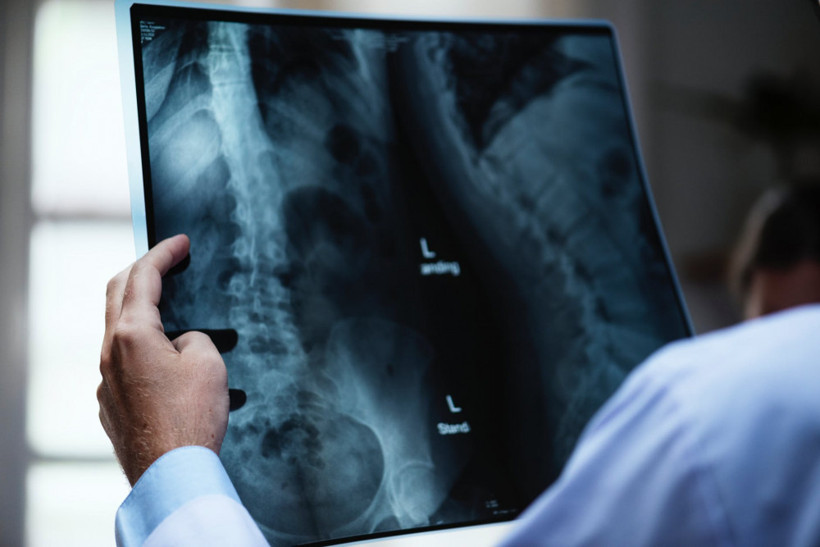

Kırılgan kemik yapısı kan kanseri habercisi olabilir! - Resim: 1

Kırılgan kemik yapısı, şiddetli bel ağrısı, ileri yaş grubunda görülen ve kan kanseri hastalığı olan multipl miyelomanın en belirgin bulgusu olarak kendini gösteriyor.